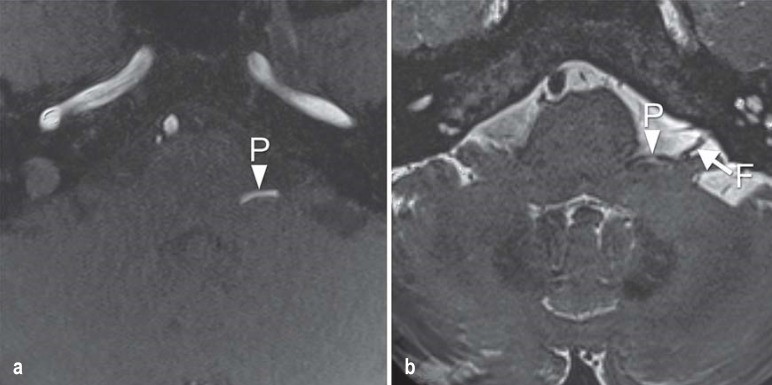

当怀疑患有神经卡压综合征时,应进行脑部磁共振成像(MRI),特别注意后颅窝。较好获得高分辨率3D-T2加权序列,如CISS(稳态建设性干扰)序列,以及3D-TOF血管造影,以便更好地区分动脉和静脉压迫。核磁共振也可以用来排除其他可能导致相同临床表现的特征,例如肿瘤或动脉瘤。